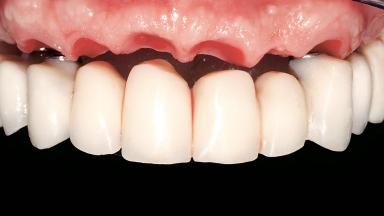

Immediate Loading of Six Implants in the Maxilla and Final Restoration with a Full-Arch CAD/CAM Zirconia FDP

A 63-year-old male patient was referred for a consultation and treatment of partial edentulism in the maxilla. The patient presented with residual anterior teeth and declined a partial removable prosthesis. He reported that the maxillary posterior teeth had been extracted due to mobility and periodontal disease two months before the consultation. The patient’s chief complaint was that his residual maxillary teeth were mobile and that he was unable to chew. The patient’s desire was a stable and comfortable fixed maxillary rehabilitation. The patient was a light smoker (fewer than 10 cigarettes/ day), and his medical history was without significant findings. He was not on any regular medication at the time of consultation. The extraoral examination revealed a normal physiognomy with a correct distribution of the facial thirds. The patient presented a low lip line, and the transition line between teeth and soft tissues was not exposed during a forced smile.

Prosthesis Type FDP

Lip Line No exposure of papillae Exposure of papillae Full exposure of mucosa margin

Defining Characteristics Fully edentulous upper jaw to be rehabilitated with an implant-borne fixed dental prosthesis